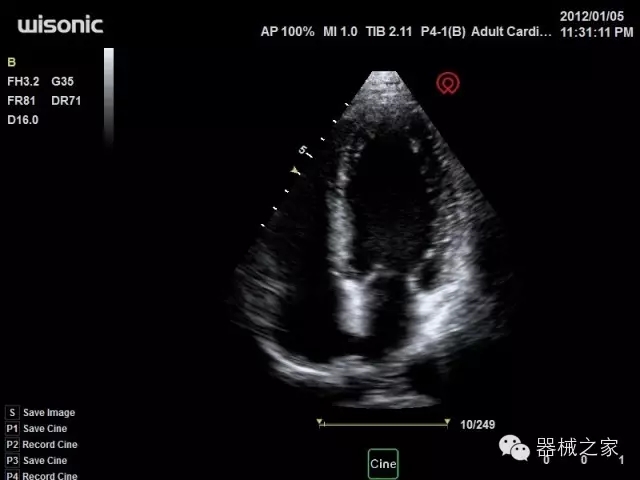

臨床圖片賞析

產(chǎn)品特點(diǎn)

·心功能綜合指數(shù)(TEI指數(shù)):用于左、右心室整體心臟收縮舒張功能評(píng)估的測(cè)量方法;

·全方位可調(diào)M型:有利于更好的觀察心腔大小及室壁階段性運(yùn)動(dòng)的異常情況;

·組織多普勒成像(TDI):TDI可定量評(píng)價(jià)心肌運(yùn)動(dòng),判斷是否有局部病變,還可評(píng)價(jià)早期的舒張功能;